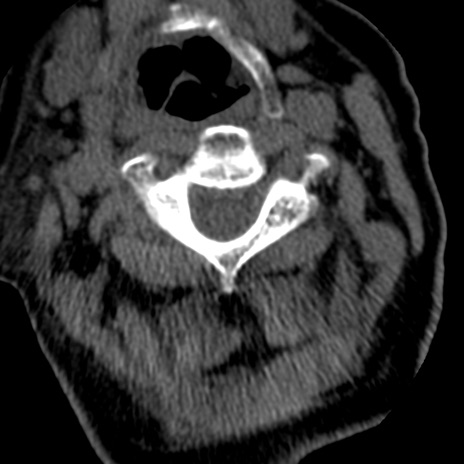

症例50 頚椎CT(横断像)

矢状断像